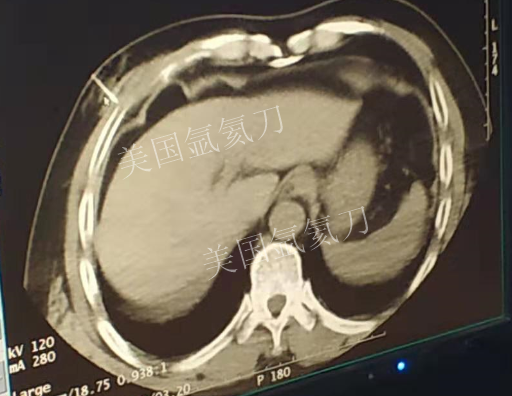

59岁男性肝部氩氦刀手术治疗